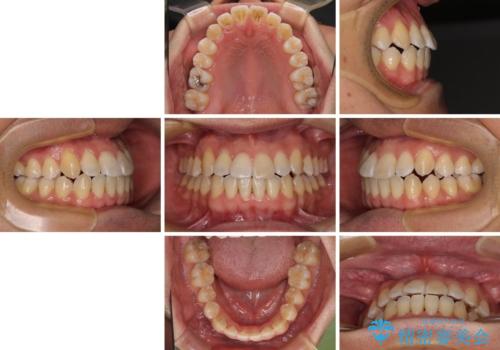

左右の八重歯が気になる ワイヤー装置での咬み合わせ改善

- 八重歯と前歯のデコボコを気にして来院された患者様です。

- 治療費の目安: 85万円(税込)費用は治療当時の料金となります

舌の突出癖がなかなか改善されず、上下前歯部の接触が得られるまでに予定の倍ほどの期間がかかりました。